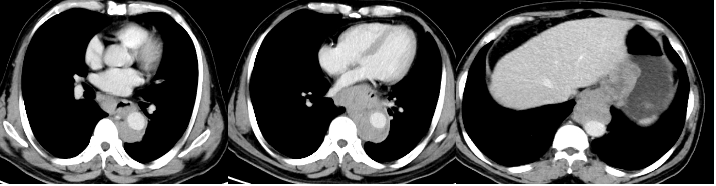

背景多学科会诊提示,卵巢癌伴胸水或胸膜受累时,胸腔热灌注是一个值得考虑的治疗方法。肿瘤细胞减灭术与腹腔热灌注和胸腔热灌注联合治疗(CRS联合HIPEC/HITHO...